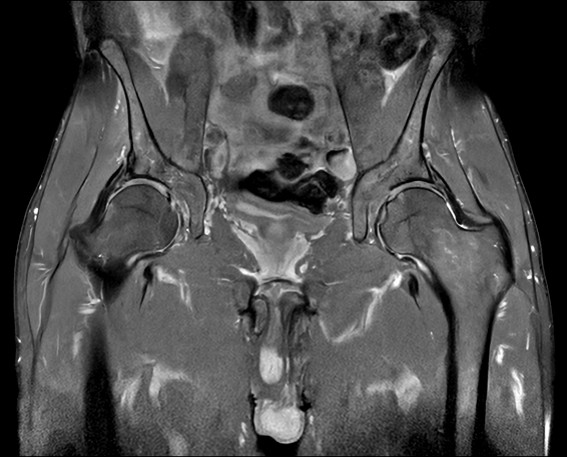

Fast bilateral hips, with SmartSpeed Precise

Fast bilateral hips_MR 5300_R11